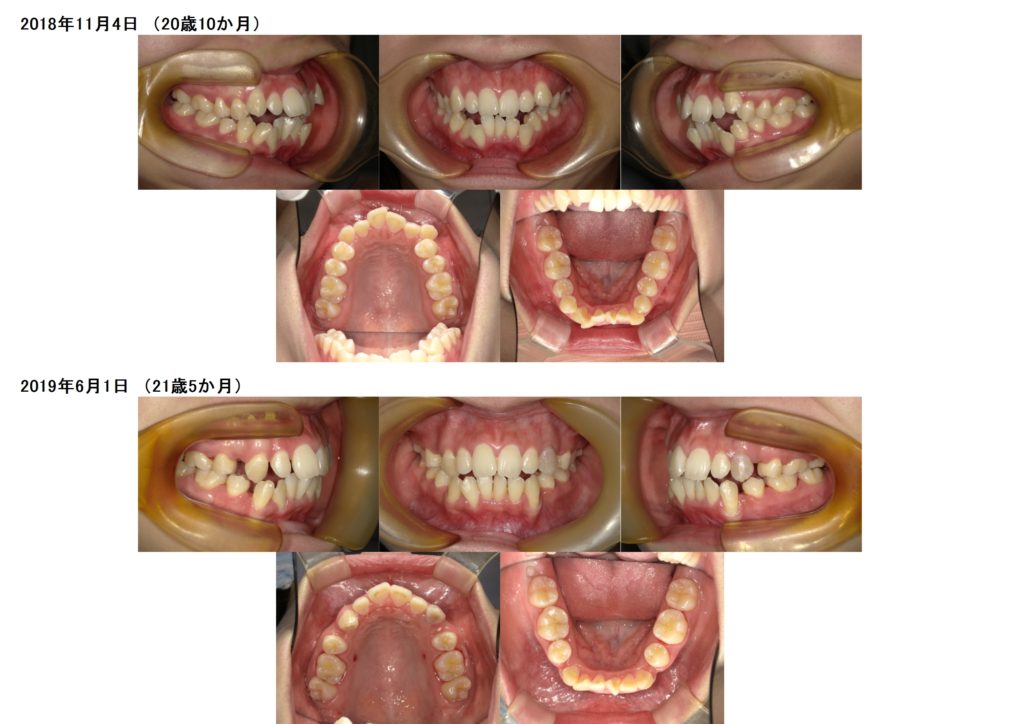

抜歯の治療例の写真

↑上下4番目の歯を左右抜歯し、約半年間側面にブラケットを装着しました。

↑抜歯、突出ケースでもしっかりとマウスピースを使うとこんなに早く変化が分かります。ここから再度噛み合わせの微調整に入るためのマウスピースを作成します。

↑ほんの細かいことですが、しっかりとゴールを迎えるために何度もポイントポイントでマウスピースの発注を行い、ゴールへと向かいます。